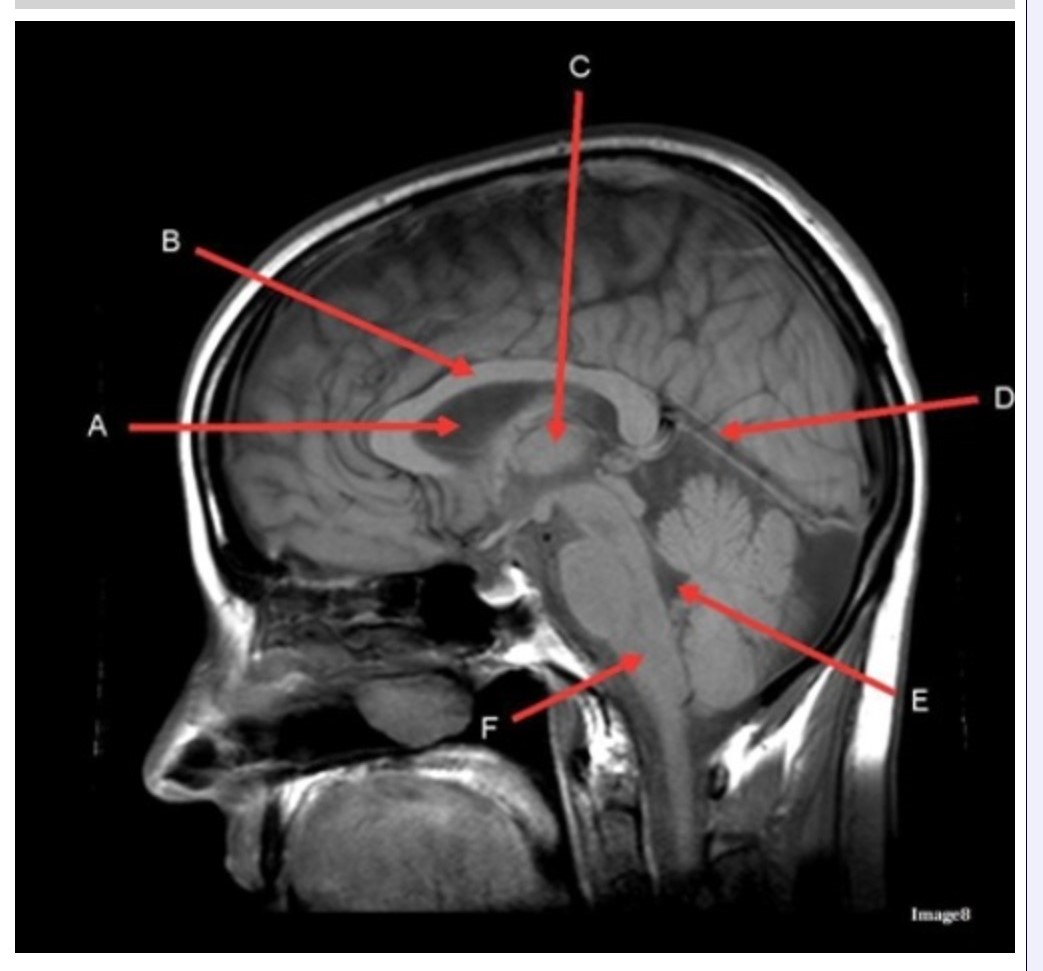

Letter C in Image 8 is pointing to:

A. Tentorium

B. Corpus callosum

C. Thalamus

D. Fourth ventricle

E. Medulla oblongata

Letter F in Image 8 is pointing to:

A. Tentorium

B. Cerebellum

C. Thalamus

D. Fourth ventricle

E. Medulla oblongata

Letter A in Image 8 is pointing to:

A. Tentorium

B. Corpus callosum

C. Hypothalamus

D. Fourth ventricle

E. Lateral Ventricle

Letter E in Image 8 is pointing to:

A. Tentorium

B. Cerebellum

C. Thalamus

D. Fourth ventricle

E. Medulla oblongata

Letter B in Image 8 is pointing to:

A. Tentorium

B. Corpus callosum

C. Hypothalamus

D. Fourth ventricle

E. Medulla oblongata

Letter D in Image 8 is pointing to:

A. Tentorium

B. Cerebellum

C. Thalamus

D. Fourth ventricle

E. Medulla oblongata

Image 8 is an example of a _______ weighted sequence acquired in the _______ scan plane.

A. T1; Axial

B. T1; Sagittal

C. T2; Axial

D. T2; Sagittal